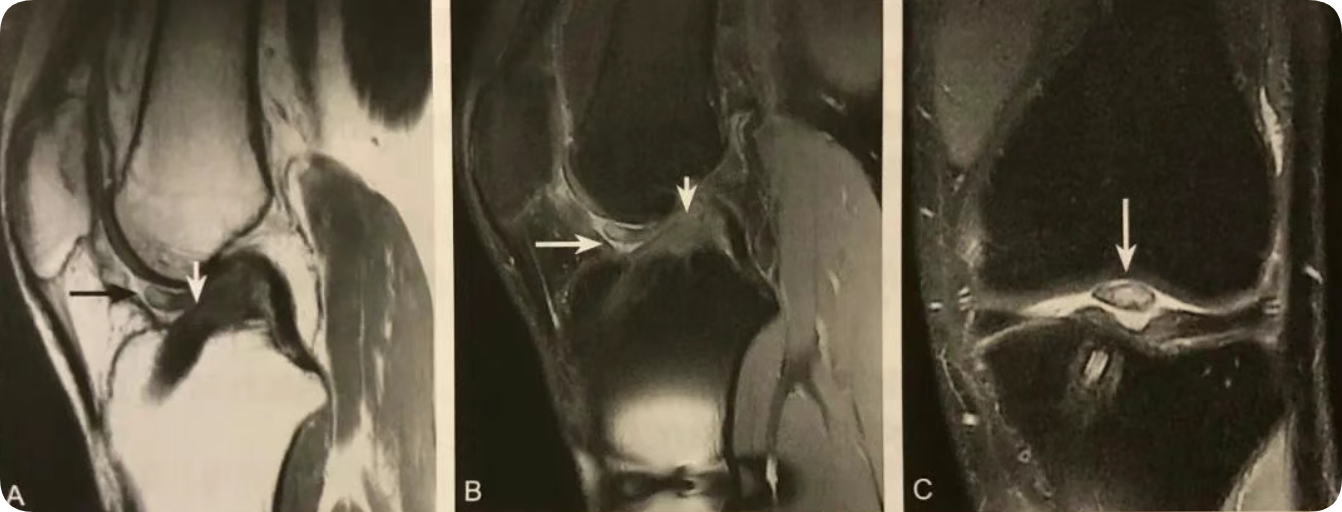

1. ACL 重建术后的一种并发症,由于局灶性纤维瘢痕增生所致;

2. 位于移植物髁间窝前方;

3. 在T2W矢状位上观察最佳;

4. T2WI 表现为边界清晰的结节状低信号,与周围关节液分界清晰。